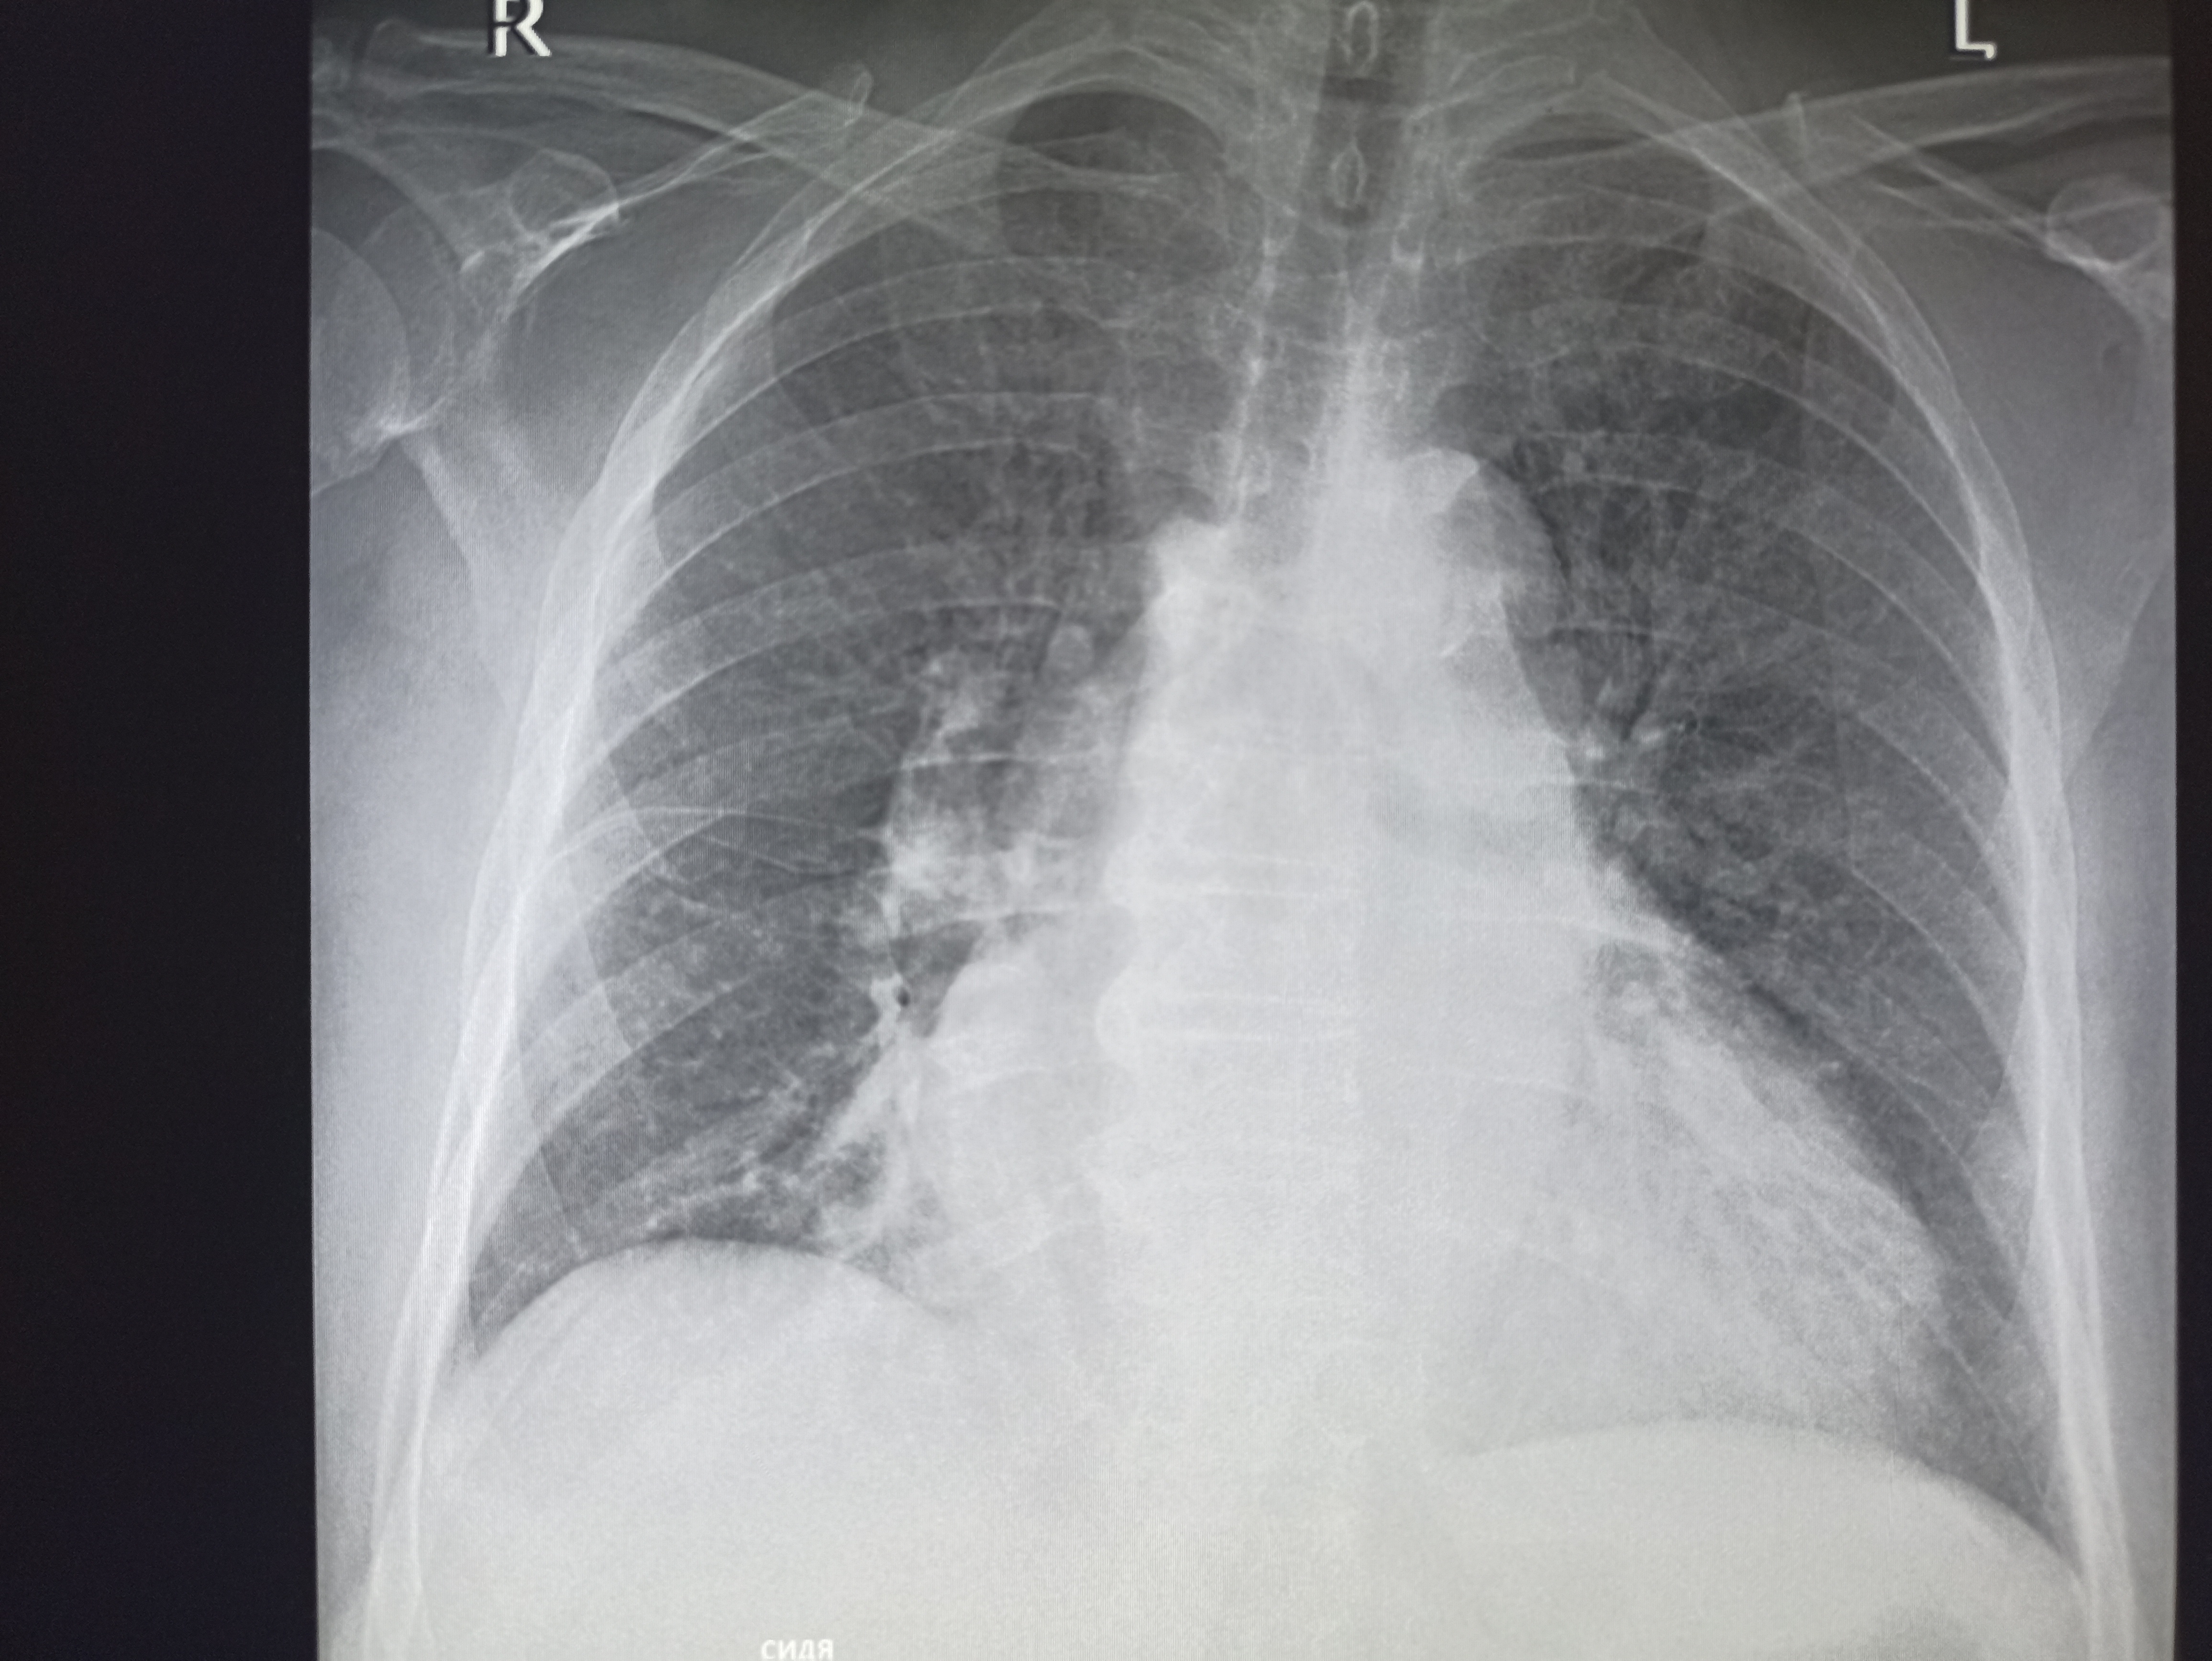

Здравствуй двачик, на прошлой неделе вышел из отпуска и уже дергается глазик, вчера сидел на работке пока поликлинику не закрыли и не все доделал. Не могу перестать кричать внутри головы! Потому мы с вами будем сегодня играть в доктора! Я буду вам показывать фоточки а вы угадывать пиздецомы! Што шпогнали! Найдите поломку!